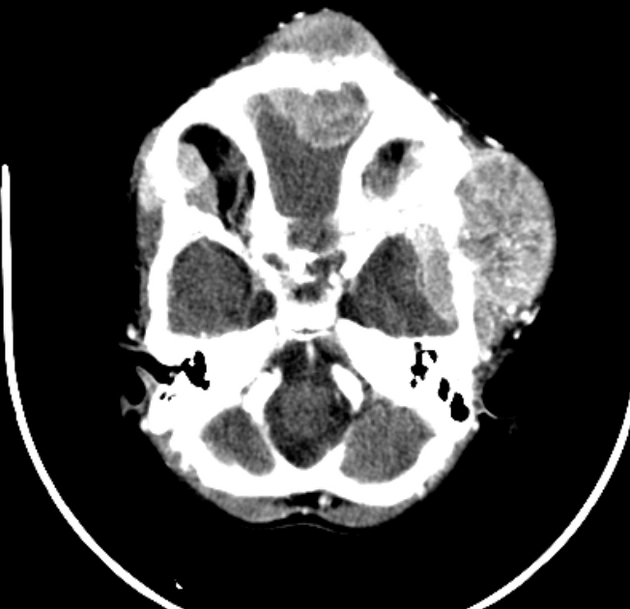

• U phôi và U nguyên bào thần kinh (Embryonal and Neuroblastic Tumors)

• U phôi sắp xếp kiểu hoa hồng (Embryonal tumor with multilayered rosettes - ETMR)

• U quái/u cơ vân dạng không điển hình (Atypical teratoid/rhabdoid tumor - AT/RT)

• U nguyên bào thần kinh di căn (Metastatic Neuroblastoma)

• U nguyên tủy bào (Medulloblastoma)